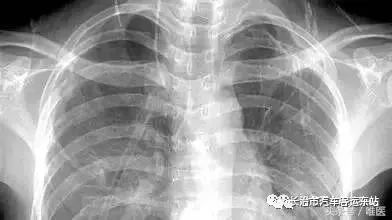

“胸片曝光”指的是使用X射线对患者胸部进行成像的过程,X射线是一种电磁辐射,能够穿透身体不同密度的组织,在胸片上,密度高的组织(如骨骼)会呈现为白色,密度较低的组织(如肺部,充满空气)呈现为黑色或深灰色,而中等密度的组织(如心脏、大血管、肝脏、脾脏等)则呈现为不同的灰度,通过观察这些影像信息,医生可以判断是否存在异常,如肺炎、肺结核、肺癌、心肌肥厚、胸腔积液、肺气肿、胸膜病变、骨骼异常等。

- 观察肺部: 正常肺野应该是深灰色(含气),如果看到大片白色或混杂区域,可能提示炎症、积液或纤维化,黑色区域如果异常扩大,可能提示肺气肿。

- 观察心脏和大血管: 心脏轮廓在胸片上大致呈“靴形”或“梨形”,如果心脏轮廓增大,可能提示心脏功能或结构问题,主动脉弓是胸片上重要的血管标志,增宽可能提示动脉瘤。

- 观察胸廓和骨骼: 肋骨、胸椎、锁骨等结构应排列整齐,无扭曲或异常增厚,胸腔内软组织密度均匀。